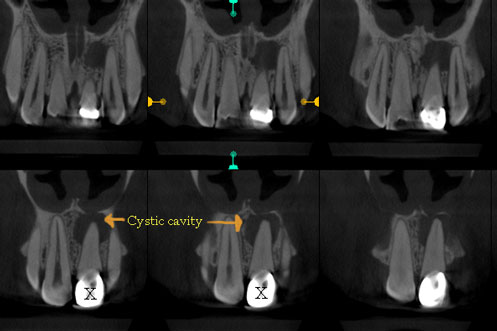

Cyst Enucleation